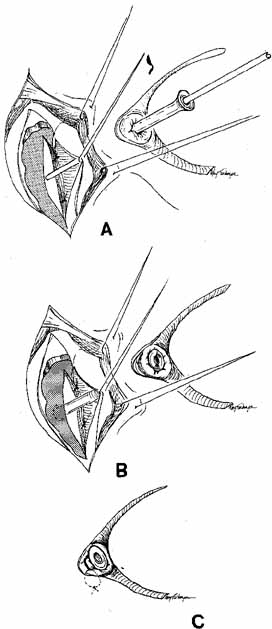

Fig. 56 Open bypass tube method. A. Surgery is the same as for a routine dacryocystorhinostomy (DCR) until

the formation of mucosal flaps. B. A portion of the caruncle can be excised to provide more room for the

Jones tube collar. The needle is removed, and the Jones tube inserted

over a straight probe. C. A 6–0 nonabsorbable suture is tied around the collar to the lid

on the palpebral surface. Fig. 56 Open bypass tube method. A. Surgery is the same as for a routine dacryocystorhinostomy (DCR) until

the formation of mucosal flaps. B. A portion of the caruncle can be excised to provide more room for the

Jones tube collar. The needle is removed, and the Jones tube inserted

over a straight probe. C. A 6–0 nonabsorbable suture is tied around the collar to the lid

on the palpebral surface.